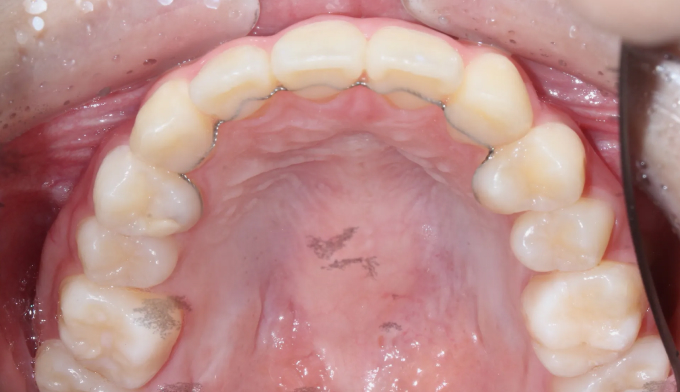

틀어진 이들을 원래의 위치로 당겨서 위아래 중심선을 맞춰줍니다.

총 교정기간은 17개월 소요되었습니다.